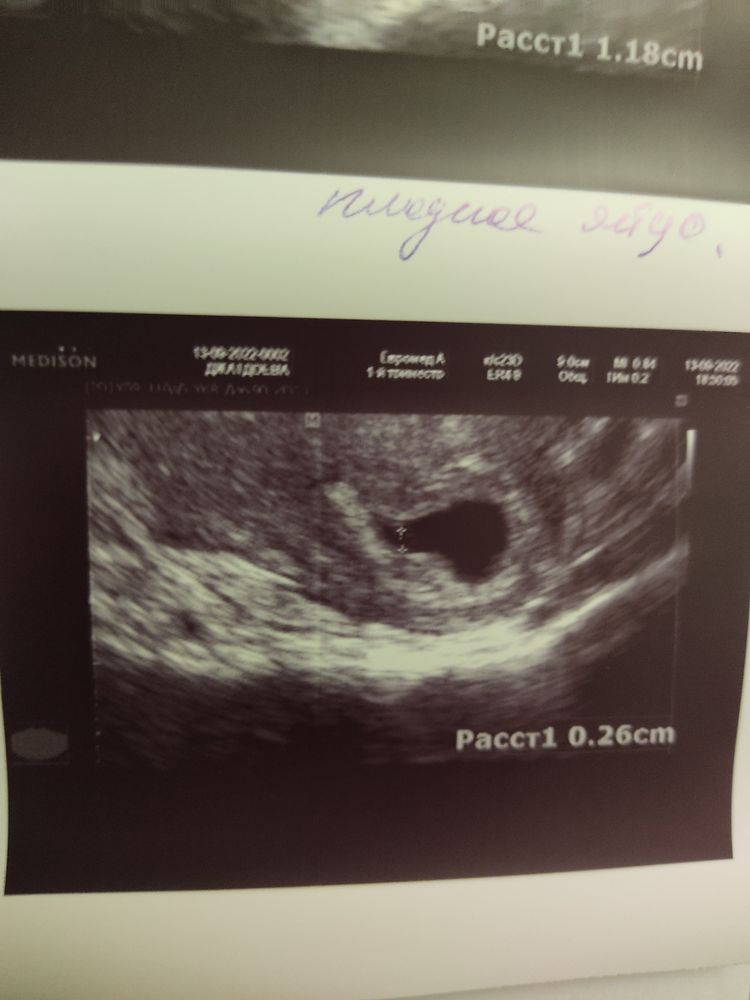

Девочкииииии. Поздравьте меня. Наконец нашли эмбрион и сердцебиение 😭

Ууууух, эмоции переполняют. Как же я переживала. Три месяца назад была замершая беременность. Снова получилось забеременеть. На срокне акушкрском 6.4 пошла на УЗИ.

Был желточный мешочек 2.5 и плодное яйцо 12 мм. Но эмбриона не было. По УЗИ поставили 5-6 недель, отставание по сроку и угрозу замершей беременности.